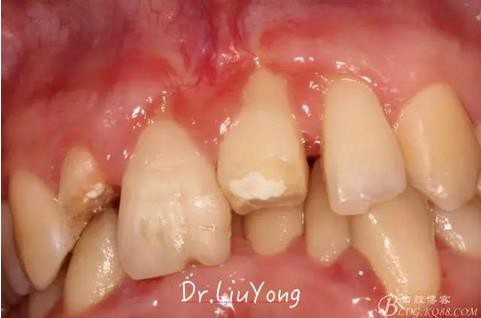

檢查:面部對(duì)稱無(wú)腫脹畸形,張口度正常,口內(nèi)檢查可見(jiàn)A2牙冠缺失,可見(jiàn)直徑約1.5mm左右穿髓孔,冷熱刺激痛+,叩痛+,探痛+,近中斷面探診位于齦下1.5mm,A1B1B2松動(dòng)2-3度,B1牙冠缺失1/2,冷熱刺激痛-,叩痛+,B2牙冠完整,A2-B2牙齦紅腫,探診極易出血,全口口腔衛(wèi)生差,牙結(jié)石++,A1B1之間牙齦乳頭紅腫嚴(yán)重,B1唇側(cè)牙齦萎縮明顯,牙齦邊緣可見(jiàn)縫線兩處,局部有滲出,齦緣冠方1mm處見(jiàn)白色骨塊,松動(dòng),觸痛明顯,觸及骨塊時(shí)可見(jiàn)B1及B2近中唇側(cè)牙齦動(dòng)度,B1B2之間唇側(cè)牙齦乳頭缺失,B2近中根面可見(jiàn)大量牙結(jié)石。重度深覆合,牙尖交錯(cuò)位時(shí)C3-D2咬至上前牙腭側(cè)齦緣,A1切端咬至C12唇側(cè)齦緣。其余牙齒未見(jiàn)明顯異常。

術(shù)前口內(nèi)照片如下: